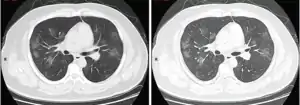

وجدت دراسة أُجريت في الصين أن التصوير المقطعي المحوسب أبدى ارتشاحات بمظهر الزجاج المغشى في 56% من الحالات، لكن 18% منهم لم يبدوا أي علامات شعاعية. قُبل 5% منهم في وحدات العناية المركزة، واحتاج 2.3% إلى دعم تنفسي ميكانيكي وتوفي 1.4%. تعتبر علامة الزجاج المغشى المحيطية وثنائية الجانب أكثر الموجودات نوعية على التصوير المقطعي المحوسب. يعتبر التكثف والارتشاحات الخطية وعلامة الهالة العكسية من الموجودات الشعاعية الأخرى للمرض.[66][67]

في البداية، تكون الآفات مقتصرة على رئة واحدة، لكن ومع انتشار المرض، تبدأ العلامات بالظهور في الرئتين لدى 88% من «المرضى المتأخرين» المشاركين في الدراسة الإحصائية (المرضى الذين فصلت بين ظهور الأعراض لديهم وإجراء التصوير المقطعي المحوسب مدة 6 أيام إلى 12 يومًا.[67]

تصوير مقطعي محوسب لمصاب بالمرض

تصوير مقطعي محوسب لمرحلة سريعة من المرض